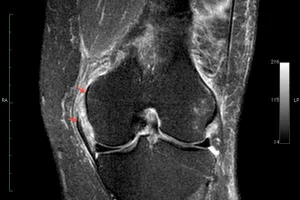

- Ressonância magnética – esse exame possui a capacidade de caracterizar com detalhes as partes moles de forma não invasiva, e tornou-se excelente método na avaliação da cartilagem. Mas nem todas as condições de lesões ou desgastes na articulação poderão ser avaliados por esse método, pois dependem do grau de comprometimento.